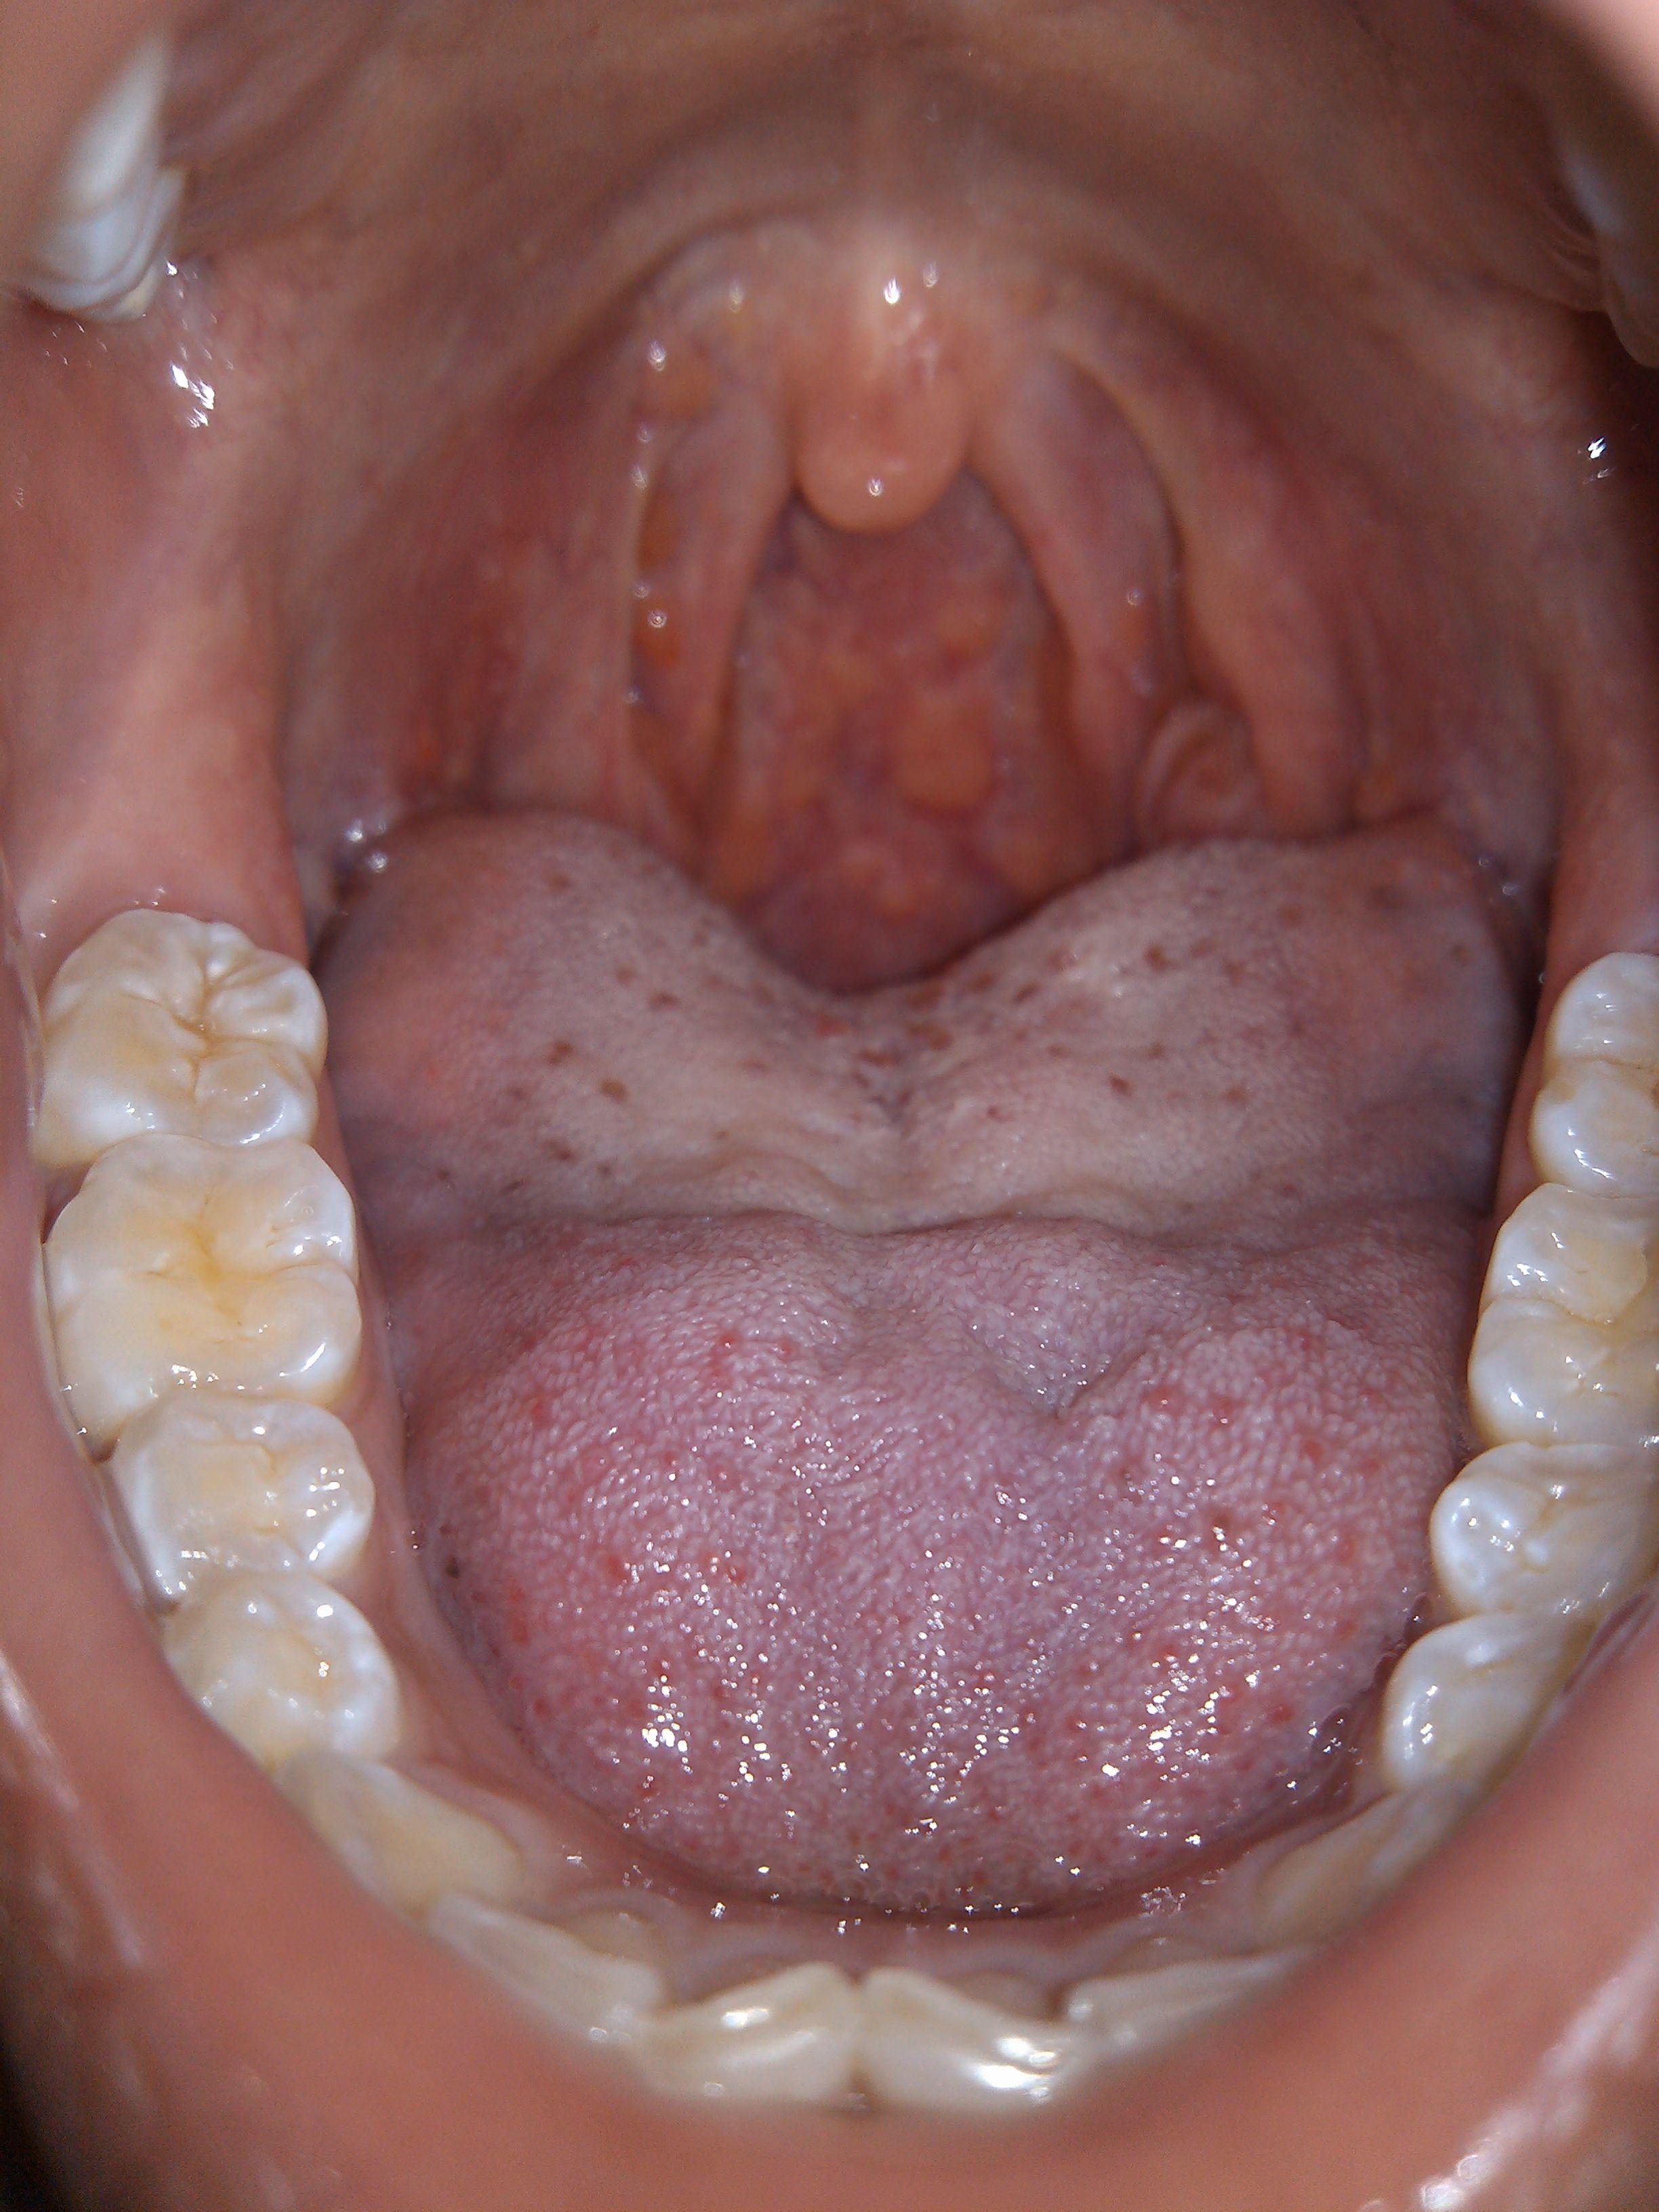

扁桃体肥大是什么样的扁桃体肥大最佳及最好治疗方法

问:扁桃体二度肿大. .